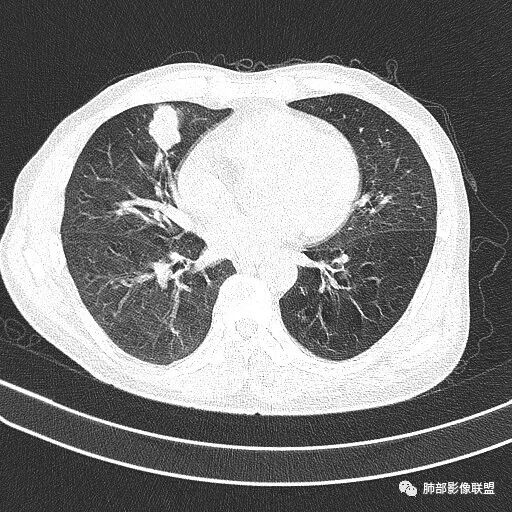

晨读病例  患者老年男性,因腰腹部疼痛3周,排尿困难1周入院。查尿常规及C反应蛋白提示泌尿系感染。肿瘤标志物NSE、细胞角蛋白19片断稍升高。胸部CT:右肺中叶内侧段类圆形肿块影,浅分叶,部分层面见深分叶,胸膜牵拉及支气管截断征象,边界清,密度低,无强化,且垮叶裂。综合考虑恶性病变,类癌及小细胞可能性大,鉴别囊肿等良性病变肺囊肿。

实性还是GGO?      实性

边界清楚、光滑?     光滑清楚,浅分叶,无明显毛刺

与支气管关系如何?   能看清楚吗

1.右肺中叶孤立不规则块影,浅分叶,未见液化或钙化,未见毛刺,未见脐凹,未见明显胸膜牵拉。

2.近肺门侧隐约见支气管截止。

3.外侧可见血管进入,病灶局部轻度强化。

上述均不符合光滑类圆形的支气管肺囊肿,也不符合典型的类癌,切不可先入为主。也不符合转移瘤。

4.肺门纵隔未见增大淋巴结。如此体量的肺块,没有增大淋巴结,不符合小细胞肺癌的生物学行为。

5.未见卫星灶,未见支气管增厚,结核也缺少支持点。

综上,应当鉴别的主要为肺鳞癌及结核灶